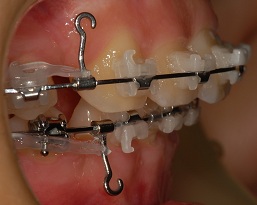

발치공간이 정말 눈에띄게 줄어들어서!

오른쪽은 거의 다 닫혔구 왼쪽만 닫히면 오라픽스 교정기를 빼는건가?!!?라는 꿈에 부풀어 잇어요ㅎㅎㅎ

이번에도 발치 공간을 줄이기 위해 고무줄을 바꿔끼고 돌아왔습니다.

정면 사진

옆면 사진